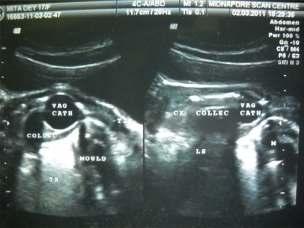

Based on the above criteria, 56 patients were selected in our study First of all vitals were checked. In severe epistaxis, first of all bleeding was controlled by nasal packing and patient was made haemodynamically stable. When the bleeding was controlled, detailed history of the patient was taken followed by general and otorhinolaryngology examination including thorough anterior rhinoscopy Laboratory investigations were done to rule out any systemic causes for epistaxis Investigations like haemoglobin estimation, total and differentialleucocytecount,plateletcount,ESR,bleeding time, clotting time, prothrombin time, a PTT, renal function tests, liver function tests, blood grouping were done routinely When no bleeding points were seen on anterior rhinoscopy and no systemic cause was found out; nasalendoscopywasperformedwithnasalendoscopes.

0 and 30 rigid nasal endoscopes of 2.7 mm and 4 mm diameterwereused.Lightcottonpledgetssoakedwith4% lidocainewasused.Noadrenalineorpriornasaldropswas usedandnoextrapressurewasexertedtoavoidmissingof the bleeding points.Then diagnostic nasal endoscopy was undertaken in three steps. The first step consisted of an inspection of nasal vestibule, nasopharynx and inferior nasal meatus. This was followed by an examination of sphenoethmoidal recess and superior meatus Finally, an examination of middle meatus was done. If nasal mass was found, CT scanwasdoneafterwards.

Mostpatientsinoursrudywereintheagegroupof2130 years (Fig 1). There were 15 female patients and 41 male patients. The most common cause of epistaxis was bleeding point in the crevices of the lateral nasal wall (32%),followedbybleedingulcerinthecrevicesoflateral nasal wall (16%), bleeding ulcer posterior to deviation of septum (14%), angioma in lateral nasal wall (13%), septal spur (11%), congested polyp in middle meatus (9%), angiofifbroma just posterior to middle turbinate (5%) (Table 1).All of them were treated with endoscopic nasal cautery,selectivenasalpacking,polypectomy,excisionof angioma,sphenopalatinearterycauterization,spurectomy or excision of angiofibroma (Table 2). All patients had successful control of epistaxis No significant complication or morbidity has been noted in the postoperative follow-up period of 1 year Seven patients hadanteriorepistaxisinfollowupperiodeitherduetonose picking or nose blowing.All of them were managed with conservativetreatment(Fig2&3).

The anterior and posterior rhinoscopies give a very restricted view of the nasal cavity, resulting in poor visualizationofcertainareas.Duetothisreason,thecause of the epistaxis many a times remains an enigma Even if the area is seen, it is difficult sometimes to apply direct pressuretoensurestoppageofbleeding.Traditionallythe treatmentoptionswereoneormoreofthefollowing:nasal packing, septoplasty, and ligation of external carotid artery or internal maxillary artery Apart from high failure rates ranging from 26-52%, these procedures have 5-6 significant morbidity . Conventional nasal packing is associated with considerable discomfort, mucosal trauma and morbidity due to hypoxia. The large size of the packing material exerts pressure not only on the point of bleedingbutalsoonthenormalmucosa.Sometimeshaste instrumentationmaycauseafreshbleed Externalcarotid artery ligation is associated with risk of damage to hypoglossalandvagusnerve Thetransantralapproachto internal maxillary artery may cause damage to 5, nasolacrimal duct or infraorbital nerve Recently angiography and embolization of bleeding vessels have been added to treatment option. But it requires expertise of an experienced interventional radiologist, which is not uniformly available. Moreover, it is also associated with serious 9,10 neurologicalcomplications Regularuseofnasal endoscopy during the last decade amplified the knowledge on the aetiology and treatment of epistaxis. The bleeding source inside the nasal cavity could be more easily and accurately identified. Cauterization of the bleeding point, which was previously limited to anterior portions of the nasal cavity, could be applied to posterior regionswiththeadventofendoscope . Moreover, nasal endoscopy is the only way for preventing trauma to the normal mucosa due to Fig 3 — Clinical photograph of bleeding point over middle turbinate